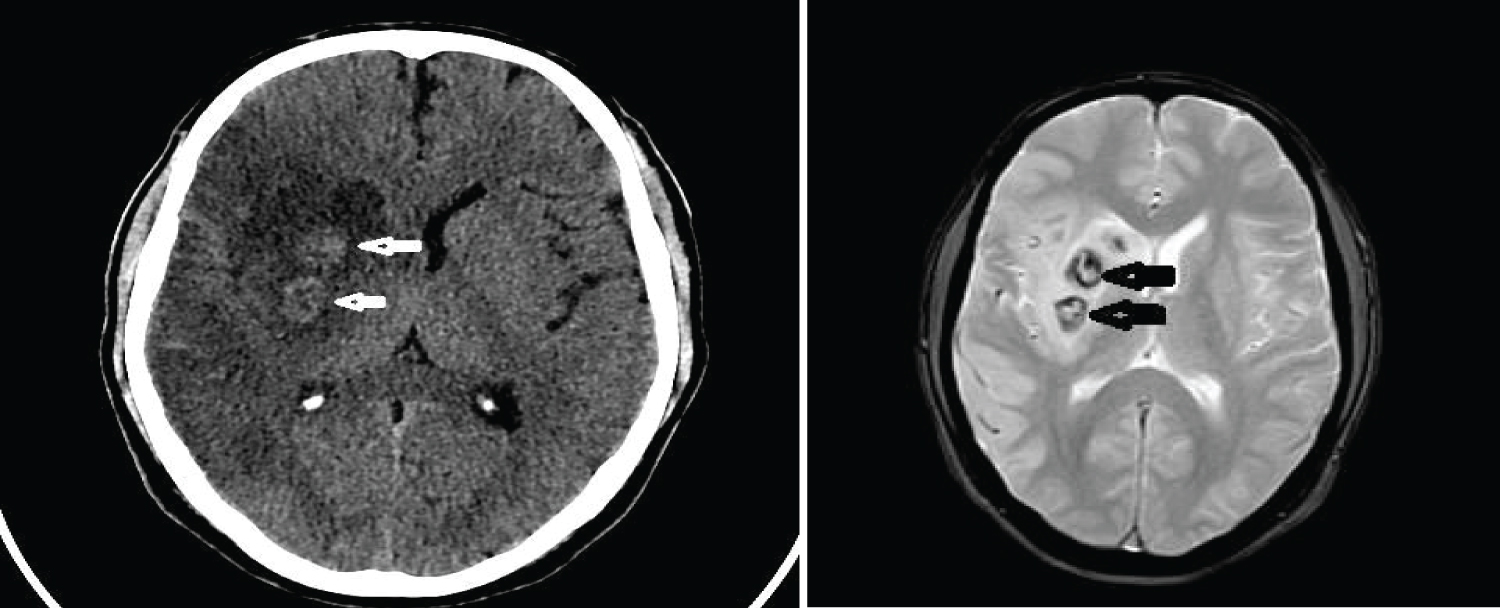

MRI brain on day six post stroke showed a wedge shaped hypodensity in the right frontal and parietal region consistent with infarct with edema and mass effect with minimal midline shift 3 mm. Hemorrhagic change was seen in the area of the basal ganglia (Figure 3 and Figure 4).

Figure 4: CT scan and MRI (FFE sequence) showing hemorrhagic transformation in right MCA Infarct. View Figure Chart 4